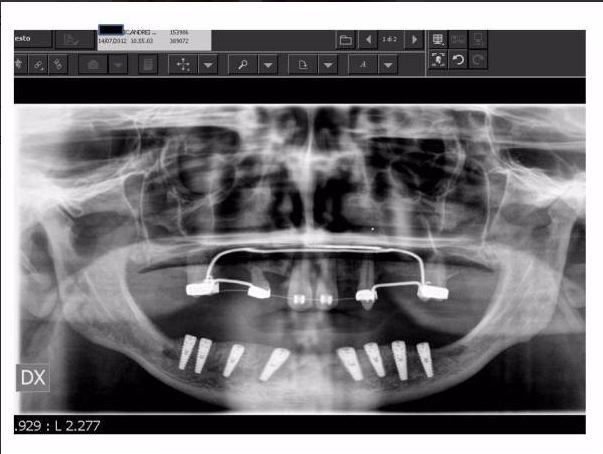

Per poter procedere con l’intervento a carico immediato è necessaria una valutazione del Prof. Giulio Gasparini specialista in Chirurgia Maxillo Facciale che mediante una prima visita iniziale, eseguendo un’ anamnesi ed esami radiografici preliminari, è in grado di determinare se ci sono le condizioni favorevoli dell’osso, in cui verranno inseriti gli impianti. Da questo momento l’esecuzione degli impianti a carico immediato e alla consegna dei vostri nuovi denti è solo una questione di poco tempo.

II fase o tempo dell'inserimento degli impianti: in questo tempo terapeutico si procede all’inserimento di impianti in titanio nelle zone edentule delle ossa mascellari e/o mandibolari. Grazie alla particolare tipologia di impianti specifici e al corretto posizionamento degli stessi, è possibile procedere direttamente con la fase protesica. L’intervento sarà completamente indolore grazie anche all’ausilio della sedazione cosciente (previa valutazione medica del nostro anestesista).

III fase, posizionamento della protesi sugli impianti: fase chirurgica: con il supporto del Laboratorio Odontotecnico Design Dentale (www.designdentale.it) e della Dottoressa Daniela Gasparini, entro poche ore saremo in grado di fissare gli elementi dentali direttamente sugli impianti inseriti durante la prima fase chirurgica. Ogni protesi è personalizzata e il risultato estetico sarà assolutamente naturale: questo è possibile anche grazie allo studio del caso preliminare effettuato pre-intervento con l’ausilio di foto ed impronte di ogni singolo paziente e tecnologia digitale CADCAM.

La visita iniziale ha in genere una durata di circa 30 minuti. Sarà il chirurgo ad accoglierti per procedere con una visita accurata in ogni aspetto: ti sarà richiesto di compilare una anamnesi medica che ci permetta di conoscere al meglio il tuo stato di salute e verranno svolti gratuitamente tutti gli esami radiografici necessari ad approfondire la tua situazione.